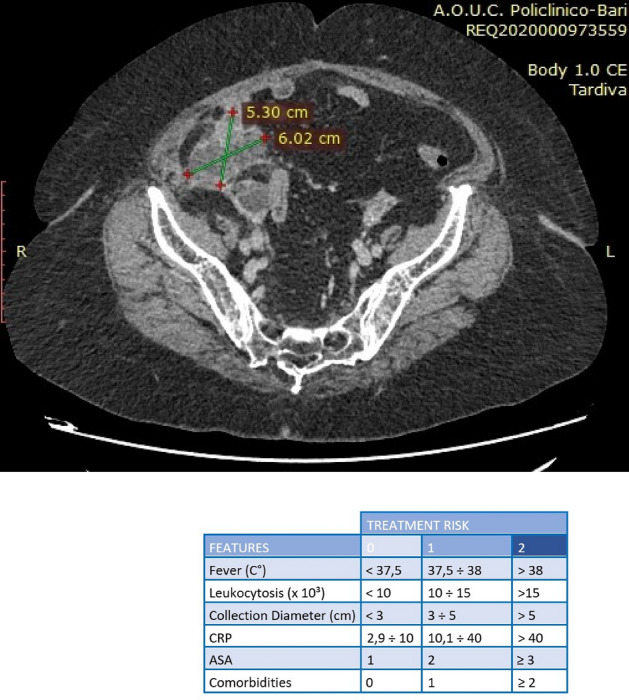

Result: The comparative analysis of the data shows a decrease in the number of presentations in ESU of AC cases during the pandemic, compared to the previous year, most often due to patients' fear of contacting the virus in the hospital environment. The median time between the onset of symptoms and the presentation in the ESU: 2020 – 14 days, 2019 – 5 days. Forms of moderate and severe AC predominated in the pandemic: GradeI—14.28%; GradeII—57.14%; GradeIII—28.57%. In 2019 GradeI—66.39%, GradeII—27.73%, GradeIII—5.88%. Laparoscopic cholecystectomy was attempted for all patients from the beginning, but the complications identified during surgery and severe forms led to a conversion rate in 2020 of 14.28%, compared to 5.88% in 2019. The severity of the cases is also observed in the postoperative complications encountered (perihepatic abscess Fig. 2. Figure 2, wound infection, bile leak; 2019—5.04%, 2020—23.21%), which required surgical reinterventions to solve them (2019: 2.52%, 2020: 10.71%). The number of deaths was significantly higher in 2020 (5.35%), compared to 2019 (0.84%).